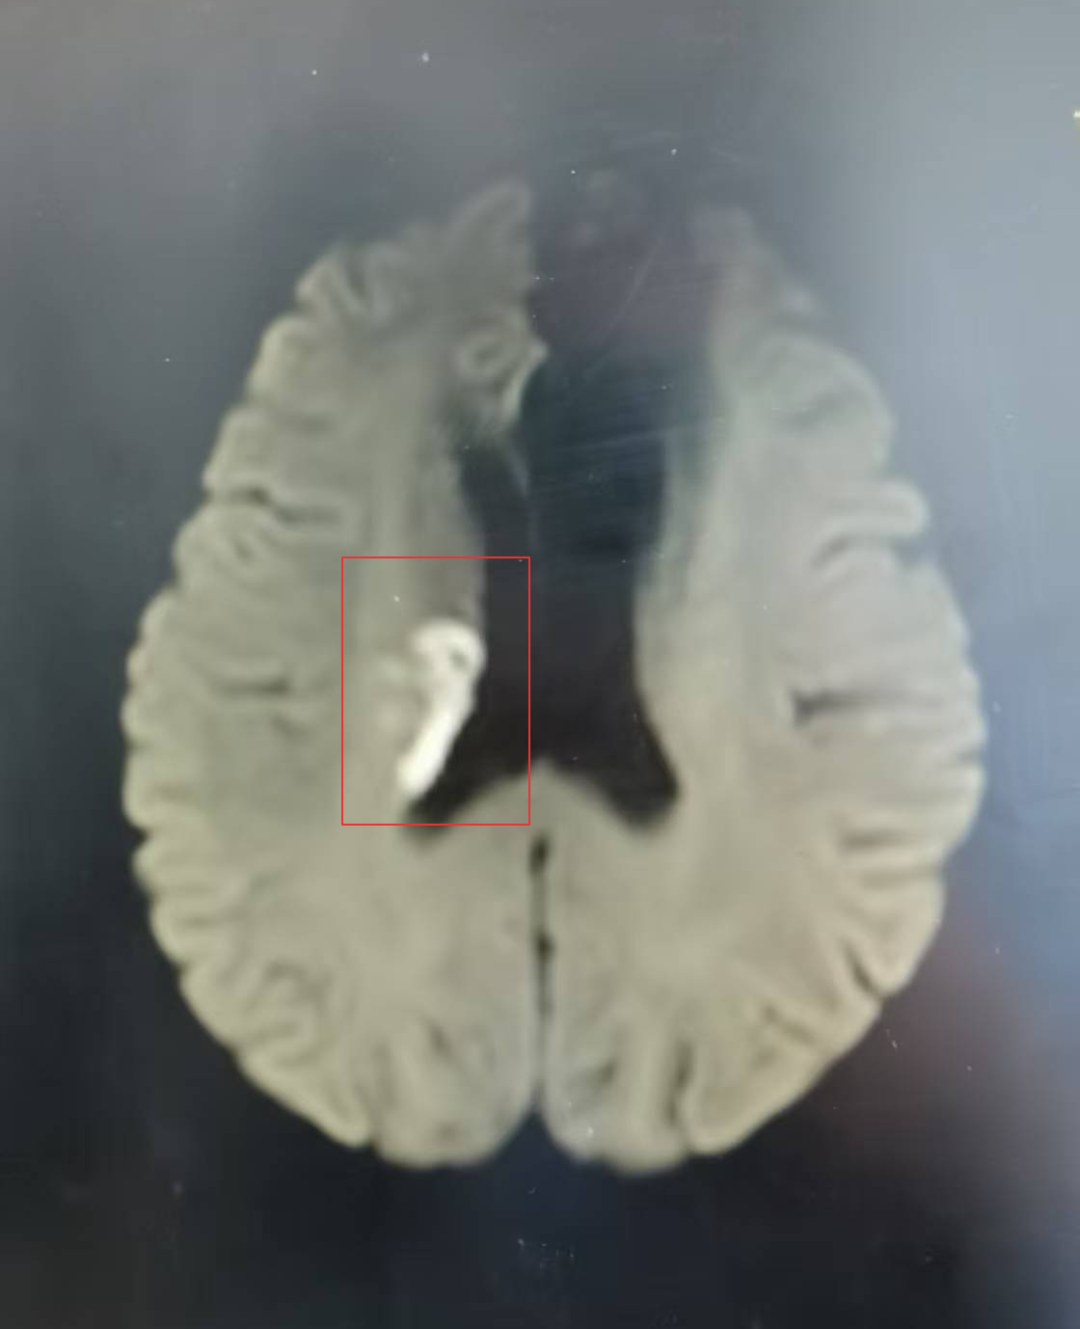

告知患者家属,考虑急性脑梗死可能性大,发病时间在溶栓时间窗内,排除溶栓禁忌症,NIHSS评分2分,家属同意溶栓治疗,于09:45给予急性缺血性脑卒中静脉溶栓治疗。

溶栓前后对比

(溶栓前后对比)

溶栓再通获益大、风险低,排除溶栓禁忌、家属沟通签字后立即给予阿替普酶静脉溶栓治疗,随即将患者置于溶栓床,进行溶栓前的准备,给予心电监护,吸氧,成功启动静脉溶栓治疗。术后李女士左侧肢体无力等症状消失,NIHSS评分0分,自述四肢有力。